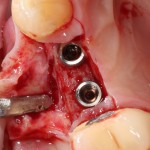

Поэтому мы начинаем с синуслифтинга:

Полученная костная пластинка заведомо больше необходимого окна. Мы потом используем ее при остеопластике. Убираем ее, видим слизистую оболочку верхнечелюстной пазухи, которую нам нужно приподнять:

приподнимаем и создаем субантральное пространство:

Затем устанавливаем имплантат. В данном случае, Friadent XiVE. Диаметром 3,4 мм — это минимальный размер импланта, который можно использовать в эстетически значимой зоне: